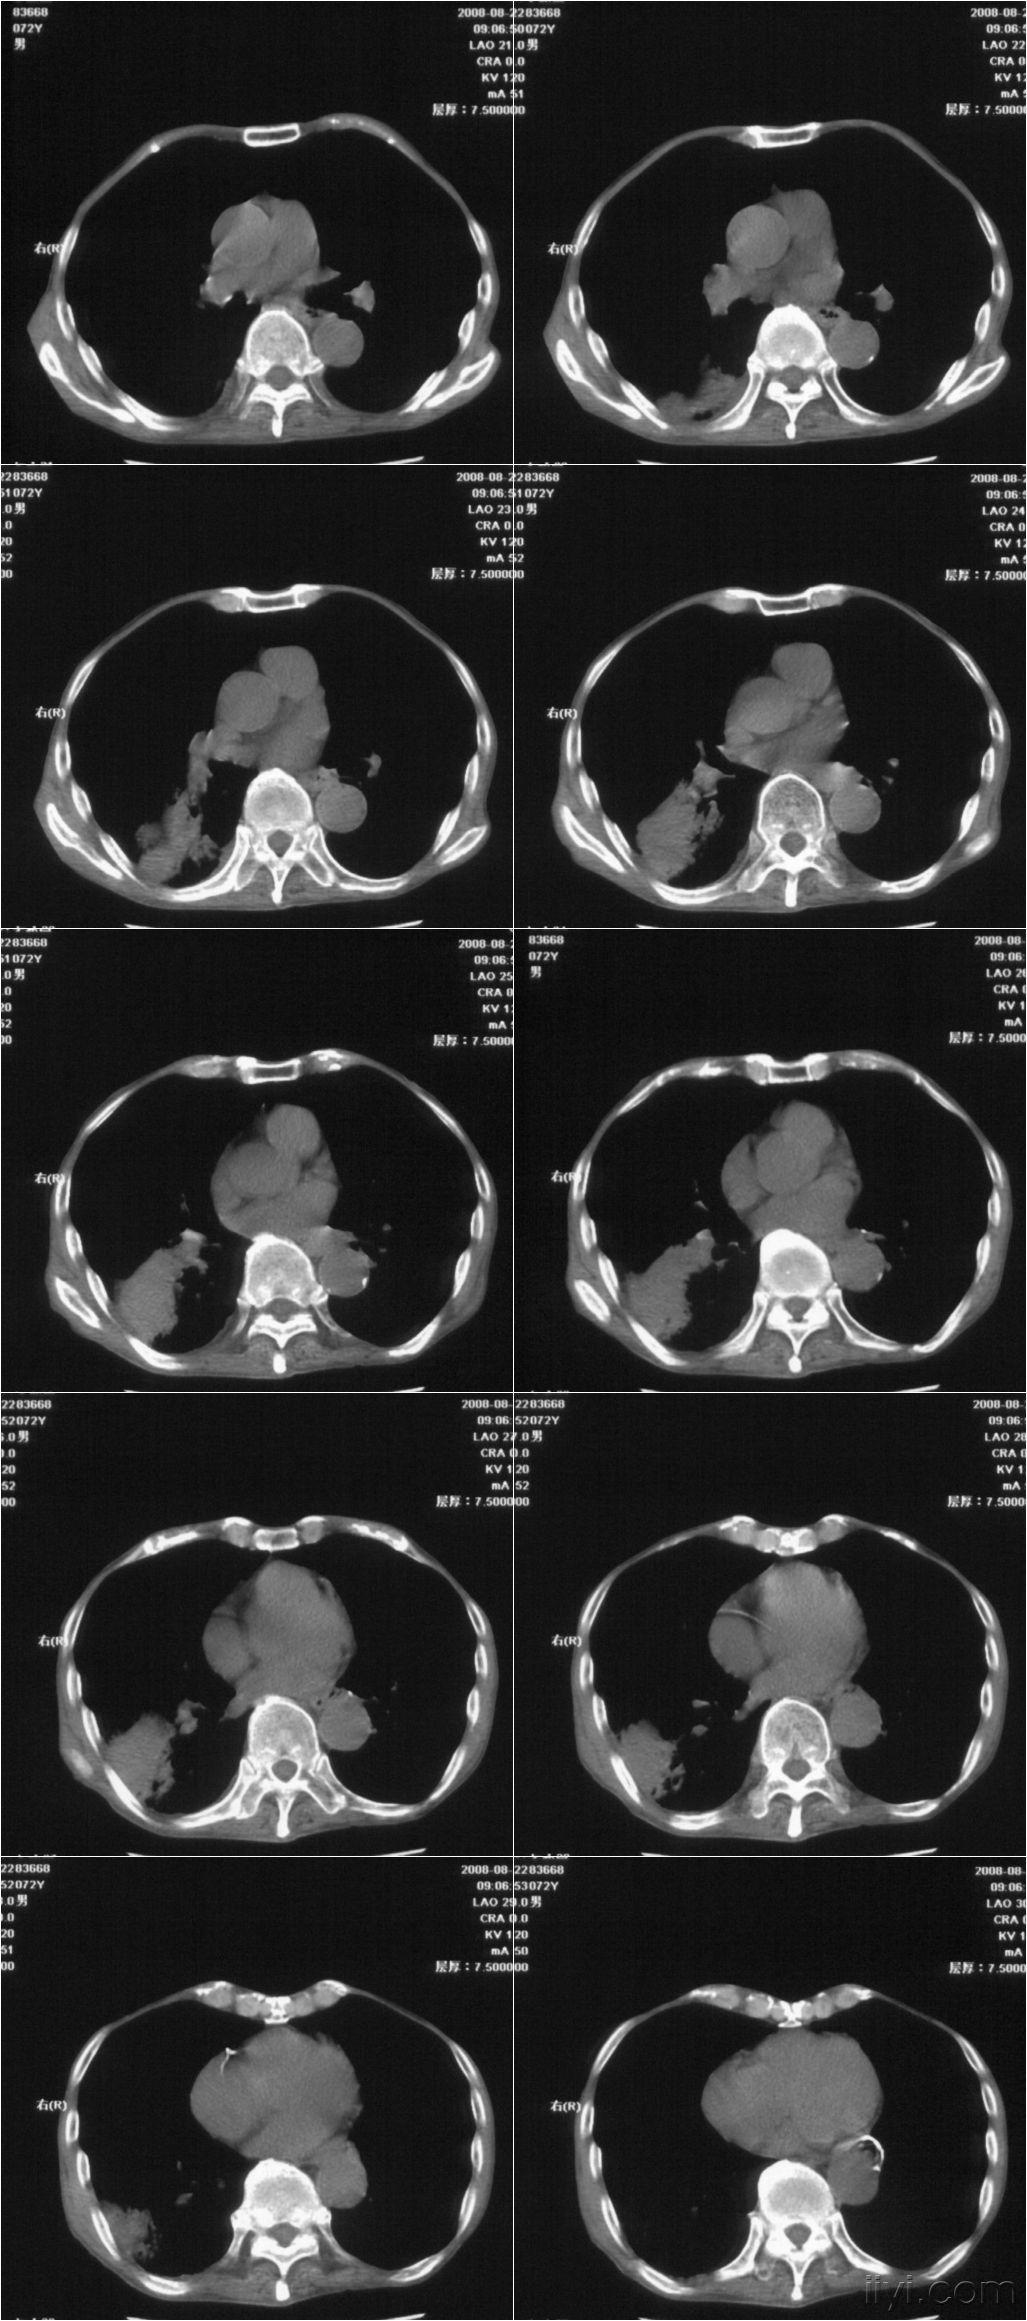

【讨论】食管癌外侵ct探讨(28367) - 影像医学和核医学讨论版 -丁香园

图片尺寸2826x2693